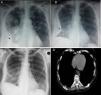

66-Year-old woman with systemic lupus erythematosus presenting with acute lupus pneumonitis. (A) Chest X-ray showing right pleural effusion (asterisk) and pulmonary consolidation in right upper lobe. (B) On the chest X-ray three days later, a right encapsulated pleural effusion (asterisk) was observed. (C) Practical disappearance of encapsulated effusion in the thoracic study two months later, with a thickening of the right costal pleura and a lateral costophrenic sinus. (D) Axial section of the computed tomography study at 6 months, at the level of the pulmonary bases with a mediastinum window was normal.

A 66-year-old woman was presented to the Emergency Department, having severe breath shortness, high temperature and chest pain. She has been suffered from systemic lupus erythematosus for 20 years, and for the last six months was using 10mg Prednisone and Methotrexate 5mg once weekly. At the examination, she was found to have elevated body temperature 38.1°C, tachycardia (120beats/min) and elevated blood pressure (160/90mm Hg). Her appearance was anorexic, diaphoretic, dyspnoeic, slightly disoriented. Her pupils were round equally with good light reaction, and her extraocular muscles were intact. She had neither neck adenopathy, nor jugular venous distention or meningismus. Precordial examination has shown no murmurs, rubs or gallops. Her breath sounds were decreased, with the right side percussion dullness. She had 2+ pitting edema to the midcalf. Examined neurologically, she had mild confusion but was nonfocal otherwise. Routine blood examination revealed normochromic normocytic anemia (haemoglobin: Hgb 11.1gm/dL), white blood cells: WBC count 24600/μL, platelets count 68000/μL and an erythrocyte sedimentation rate (ESR) 120mm in the 1st hour. Serum biochemistry revealed C-reactive protein (CRP) 3mg/dL, whereas unremarkable results were reported from urine analysis and urinoculture. Arterial blood gas analysis showed hypoxemia with respiratory alkalosis. Chest radiograph showed consolidation of the right upper lobe and a mild right-sided pleural effusion on the right side (Fig. 1A). Sputum culture, blood culture, sputum microscopy for acid fast bacilli, Mantoux test and HIV serology were negative. Treatment of the patient was started with empiric intravenous antibiotics (cefriakson, ciprofloksacin and metronidazole) accompanied with supportive care. On the 3rd day of the therapy, patient had high body temperature of 40°C and the control chest X-ray has revealed the encapsulated pleural effusion on the right side (Fig. 1B). A diagnostic thoracocentesis was performed, yielding 60mL of yellow, slightly cloudy fluid, showing a red blood cell-RBC count of 2.0×103/μL and, WBC count of 340/μL (15% leukocytes, 71% neutrophils, and 13% monocytes); pH 7.48; glucose 58mg/dL; total protein 2.46g/dL, lactate dehydrogenase 12545U/L, adenosine deaminase 51.3units/L; Ziehl-Neelsen stain negative; Gram stain and culture negative and Mycobacterium DNA polymerase chain reaction negative, with no malignant cells. Bacterial cultures were negative. Fiber-optic bronchoscopy with bronchoalveolar lavage (BAL) fluid analysis has shown epithelial cells. Since the patient had a continuously high body temperature up to 39°C and round rash emerging over the left elbow, anti-nuclear antibody (ANA) testing was performed and was positive (titer 1:1280, homogeneous pattern), with anti-ds-DNA weakly positive, while perinuclear and cytoplasmic anti-neutrophil cytoplasmic antibody (p-ANCA and c-ANCA, respectively) were negative. Serum C3 and C4 levels were decreased (30mg/dL and 7mg/dL, respectively). According to results, a diagnosis of SLE presenting with acute pneumonitis was made. On the 4th day, the patient was started with 1g intravenous methyl prednisolone once a day for 3 days, followed by tablet hydroxychloroquine 400mg daily and tablet prednisone 1mg/kg daily for 6 weeks with gradually tapering of prednisolone to a maintenance dose of 10mg daily. From two months after, her chest X-ray has shown practical resolution (Fig. 1C). At six month later, computed tomography described adhesions of the right side with no other specific abnormalities (Fig. 1D).